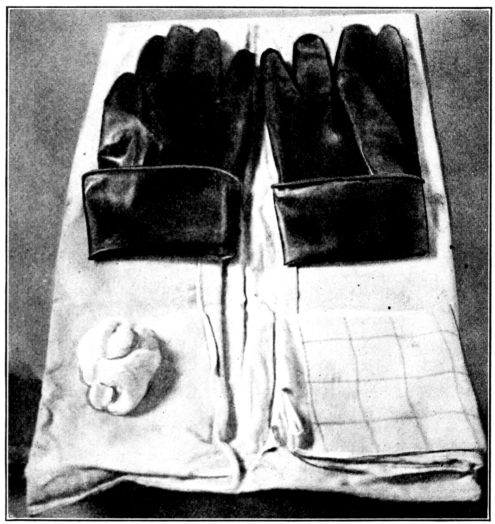

| 42. | Gloves, ready for dry sterilization | 160 |